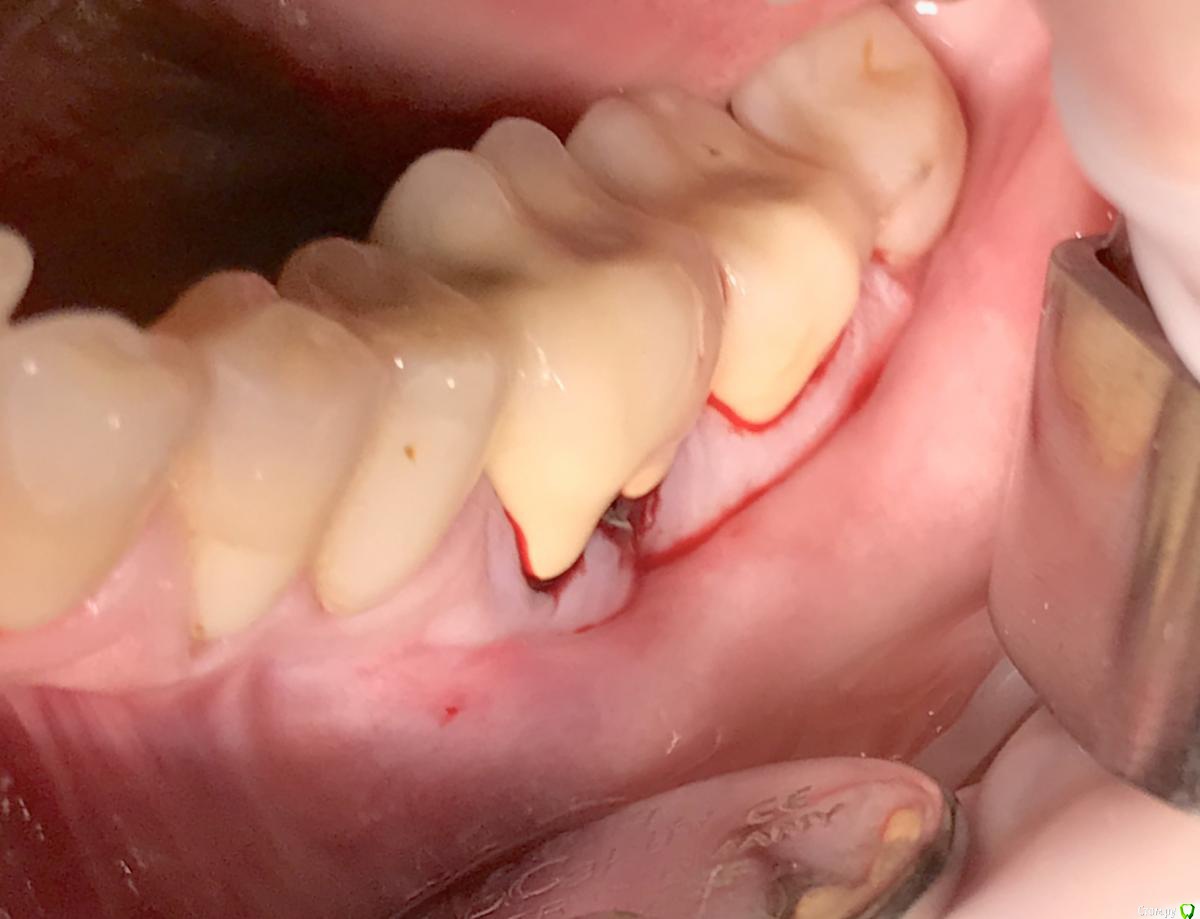

колесников Опубликовано 22 апреля, 2019 Поделиться Опубликовано 22 апреля, 2019 (изменено) И снова профайл спасает жизнь (облегчает жизнь имплантолога)Стандартная ситуация:36 периодонтит в стадии обострения с грануляциями,эксудацией,резорбцией компактной пластинки,дефицитом прикреплённой слизистой вестибулярного. Одна хирургия. Ноябрь 2018. Удаление,кюретаж,имплант Astra tech profile 4.5x9 под заглушку,торк около нуля. Вестибулярного сст,консервация графтом Sureoss 0,5 чипс с APRF,закрытие шайбой по Ноймайеру. Через неделю шайба несостоятельна-удалена. Пациентка созрела на удаление 37го. Выполнена декоронация в связи с отъездом пациентки,далее через 2 недели удаление и имплантация 37го. Промежуточный осмотр в январе. В марте установлены формирователи . Апрель контрольный осмотр. Периотест -5. Направлена на протезирование. Изменено 22 апреля, 2019 пользователем колесников 4 Ссылка на комментарий